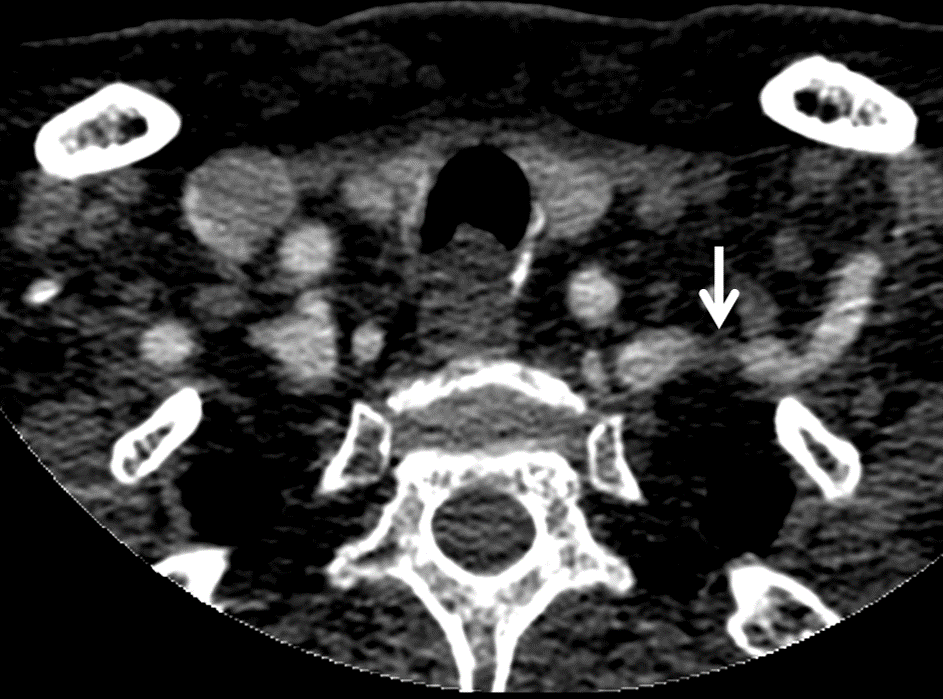

– Estenosis de la arteria subclavia izquierda (caída de presión por la existencia de una dificultad al flujo arterial). La etiología de la estenosis más frecuente es la ateroesclerótica pero también puede deberse a procesos tumorales del parénquima pulmonar o mediastino con invasión vascular.